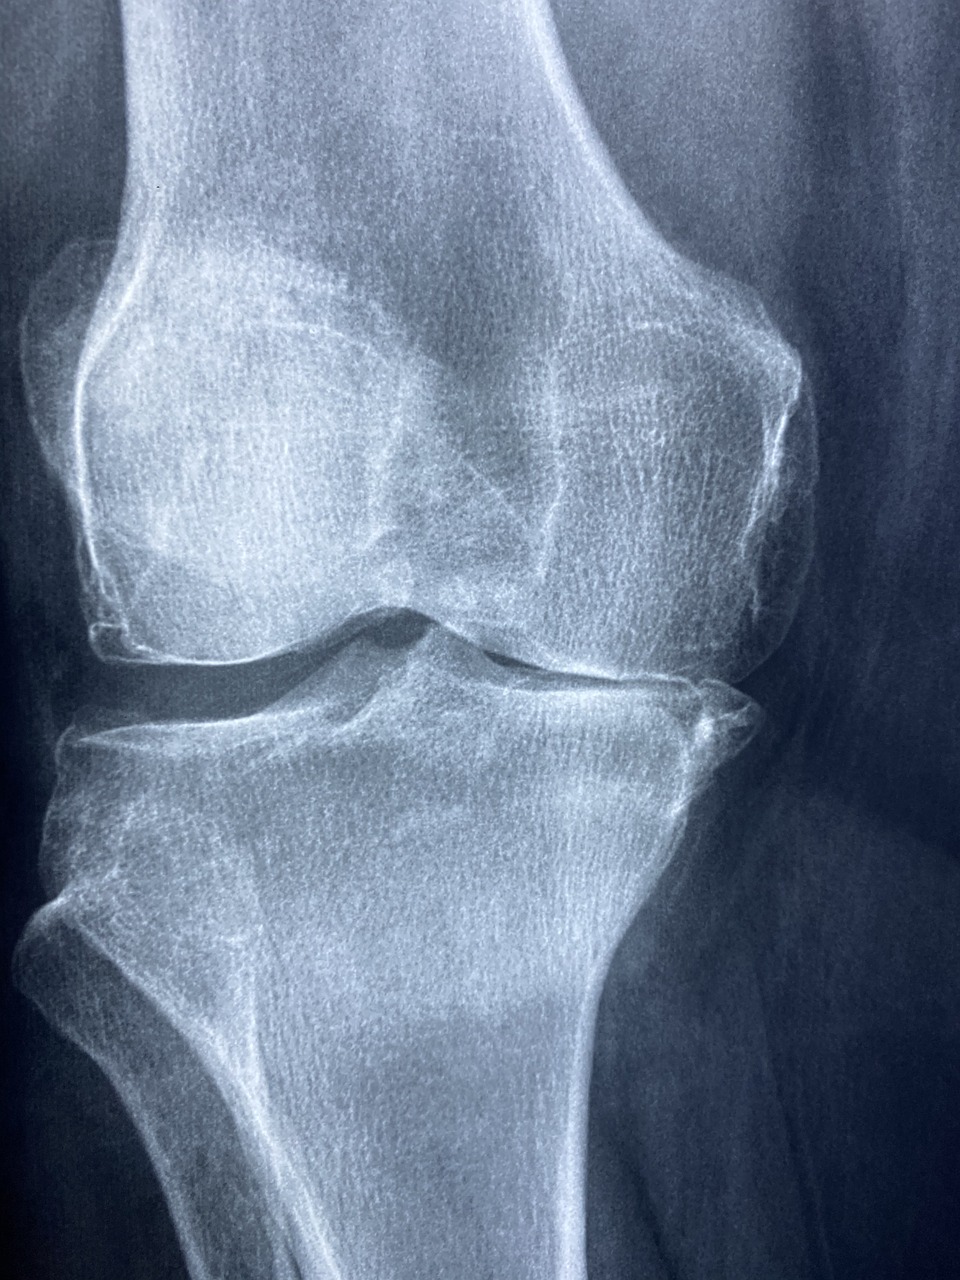

골다공증은 흔히 ‘조용한 질환’이라 불린다. 통증이나 자각 증상 없이 서서히 진행되며, 어느 날 갑작스러운 골절로 나타나 그 심각성을 인식하게 되는 경우가 많기 때문이다. 특히 중장년 여성은 폐경 이후 여성호르몬인 에스트로겐 분비가 급감하면서 골 손실이 빠르게 진행되는 시기에 진입하게 된다. 에스트로겐은 뼈를 보호하는 중요한 역할을 하는 호르몬으로, 폐경 이후 그 보호막이 사라지며 골다공증 위험이 급격히 증가하는 것이다. 우리나라는 평균 폐경 연령이 약 49세 전후로 알려져 있으며, 이 시기 이후 골밀도는 눈에 띄게 감소하게 된다. 문제는 골밀도가 줄어들더라도 일상생활에서 특별한 불편을 느끼지 않기 때문에 예방의 중요성을 간과하기 쉽다는 데 있다. 그러나 일단 척추나 고관절, 손목 등에서 골절이 발생하면 회복이 오래 걸릴 뿐 아니라 활동성이 크게 제한되고, 심할 경우 장기적인 요양 생활로 이어질 수 있다. 이는 단순한 골격의 문제가 아니라 삶의 자율성과 직결된 중대한 건강 문제이다. 골다공증은 유전적 요인이나 식습관, 흡연, 음주, 신체활동 부족 등 다양한 원인으로 발생할 수 있지만, 예방 가능한 부분도 분명히 존재한다. 특히 적절한 운동은 뼈에 기계적 자극을 주어 골밀도를 유지하고, 골 형성을 촉진하는 가장 효과적인 수단 중 하나로 꼽힌다. 운동은 단순히 근육을 단련하는 것을 넘어서, 뼈의 재생과 유지에 직접적인 영향을 주며, 골절 예방에 있어 핵심적인 역할을 한다. 이러한 배경에서 중장년 여성을 위한 골다공증 예방 운동은 선택이 아닌 필수다. 단순한 걷기에서부터 저항 운동, 균형 감각을 키우는 훈련까지 다양한 형태의 운동이 있으며, 자신의 건강 상태와 체력에 맞게 조절하여 실천하는 것이 바람직하다. 이제부터 그 운동의 구체적인 방법과 효과에 대해 자세히 살펴보고자 한다.